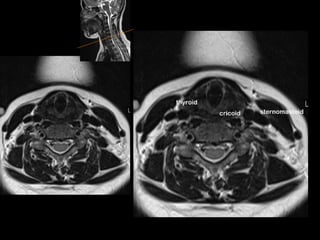

supraglottis

glottis